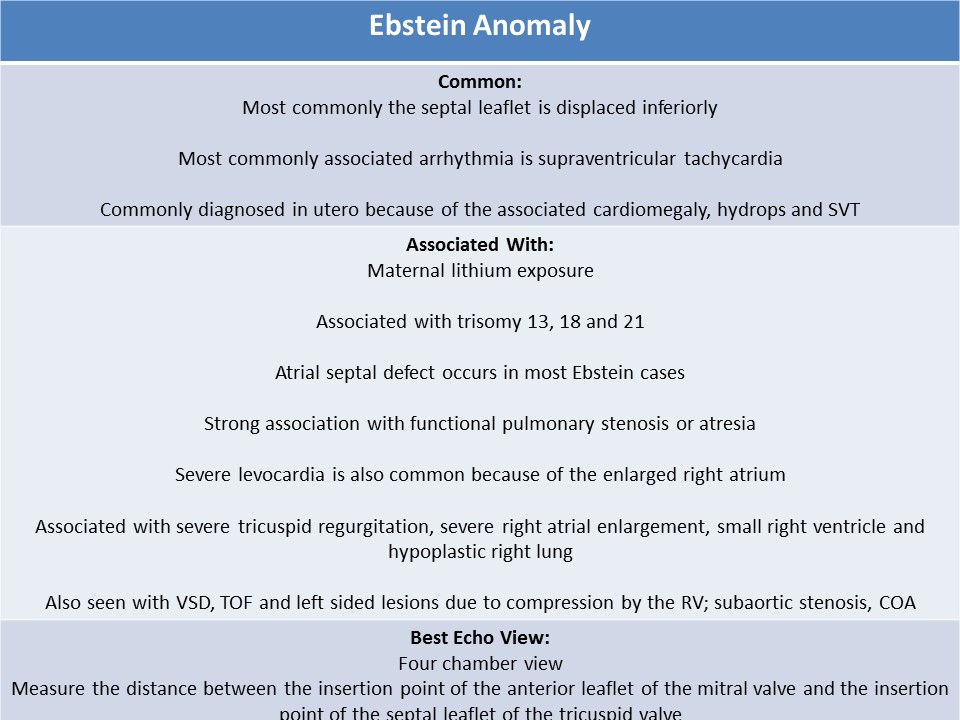

Ultrasound Registry Review Valvular Abnormalities

Ultrasound Registry Review Valvular Abnormalities